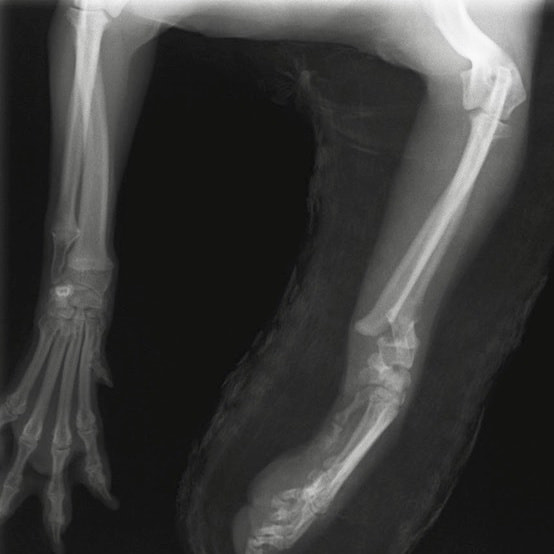

症例:交通事故による椎体脱臼

柴犬:9歳、避妊雌

交通事故直後、胸腰部に激しい疼痛、両後肢に完全麻痺を認め、シェフシェリントン徴候を呈していました。レントゲン検査において、第11-12胸椎間の脱臼が認められました。

脊髄の減圧、脊柱管の再構築・安定化を目的に、片側椎弓切除術およびMatrixMANDIBLE Plateによる椎体固定を実施しました。

隣接椎体を架橋するようにプレートを設置しました。

術後レントゲン写真